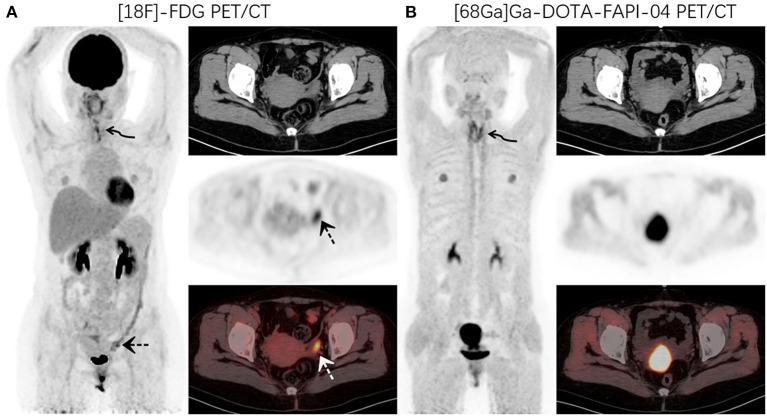

This study aimed to investigate the physiological distribution characteristics of Ga-DOTA-FAPI-04 in the ovary, and assess the feasibility of early diagnosis of primary ovarian disease with Ga-DOTA-FAPI-04 PET/CT. We retrospectively analyzed the data of patients who received F-FDG and Ga-DOTA-FAPI-04 PET/CT scanning in the Nuclear Medicine Department of our hospital within 3 days from September 2020 to January 2021. We selected the data in which ovaries showed abnormal FDG activity. Patients with abnormal ovarian FDG uptake with focus confirmed by pathological biopsy or clinical follow-up as pathological changes were excluded. The uptake of tracers (F-FDG and Ga-FAPI) was semi-quantitatively analyzed. This study included 14 patients (average age was 38.6). Physiological ovarian uptake was mostly unilateral, and there was no significant difference in SUVmax between the left and right sides (FDGt = 0.272, FAPIt = 0.592). The ovary SUVmax of FDG (4.89 ± 1.84) was statistically significantly higher than that of FAPI (1.53 ± 0.37). The Le/Li ratio on FDG is 3.38 ± 1.81, TBR is 5.81 ± 1.98, while the Le/Li ratio on FAPI is 3.57 ± 1.26, TBR is 0.94 ± 0.19. Our research shows that ovarian functional or pathological changes can be manifested as FDG avid, while Ga-DOTA-FAPI-04 has no physiological accumulation in the ovary and is not affected by the menstrual cycle. Therefore, Ga-DOTA-FAPI-04 has unique advantages in the diagnosis of ovarian diseases, and can identify them early and accurately.

本研究旨在探讨Ga-DOTA-FAPI-04在卵巢中的生理分布特征,并评估Ga-DOTA-FAPI-04 PET/CT早期诊断原发性卵巢疾病的可行性。我们回顾性分析了2020年9月至2021年1月期间在我院核医学科3天内接受F-FDG和Ga-DOTA-FAPI-04 PET/CT扫描的患者数据。我们选择了卵巢显示FDG活性异常的数据。经病理活检或临床随访证实有病变的卵巢FDG摄取异常患者被排除。对示踪剂(F-FDG和Ga-FAPI)的摄取进行半定量分析。本研究纳入14例患者(平均年龄38.6岁)。生理性卵巢摄取大多为单侧,左右两侧SUVmax无显著差异(FDG:t = 0.272,FAPI:t = 0.592)。FDG的卵巢SUVmax(4.89±1.84)在统计学上显著高于FAPI(1.53±0.37)。FDG的Le/Li比值为3.38±1.81,TBR为5.81±1.98,而FAPI的Le/Li比值为3.57±1.26,TBR为0.94±0.19。我们的研究表明,卵巢功能或病理变化可表现为FDG摄取增加,而Ga-DOTA-FAPI-04在卵巢中无生理性积聚,且不受月经周期影响。因此,Ga-DOTA-FAPI-04在卵巢疾病诊断中具有独特优势,能够早期准确识别这些疾病。